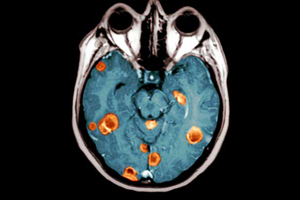

Metástasis tumorales en pulmón

Un hallazgo de bioingeniería permite transformar una amenaza en una oportunidad terapéutica única